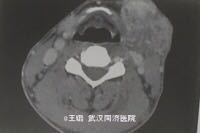

查体示左下颌包块,不可移动,触之较痛;CT示左下颌部不均匀密度影,累及下颌下腺,未见淋巴结转移,未侵犯下颌骨。